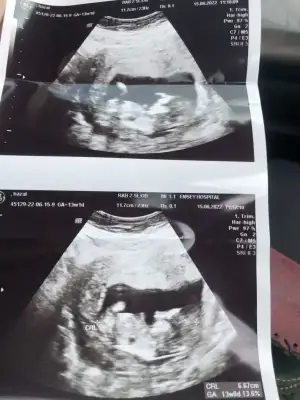

Mrb benim fistik kabugumada bakar mısınız?🤭 6+5 karından ultrason

Eklentiler

• 20220615_113030.webp

20220615_113030.webp

17,8 KB · Görüntüleme: 62